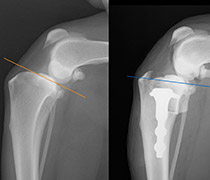

また、動物医療の高度化に伴い、外科手術の必要性は高くなっています。

当院では、腫瘍外科、整形外科、神経外科、軟部外科、眼科など様々な外科手術に対応しています。